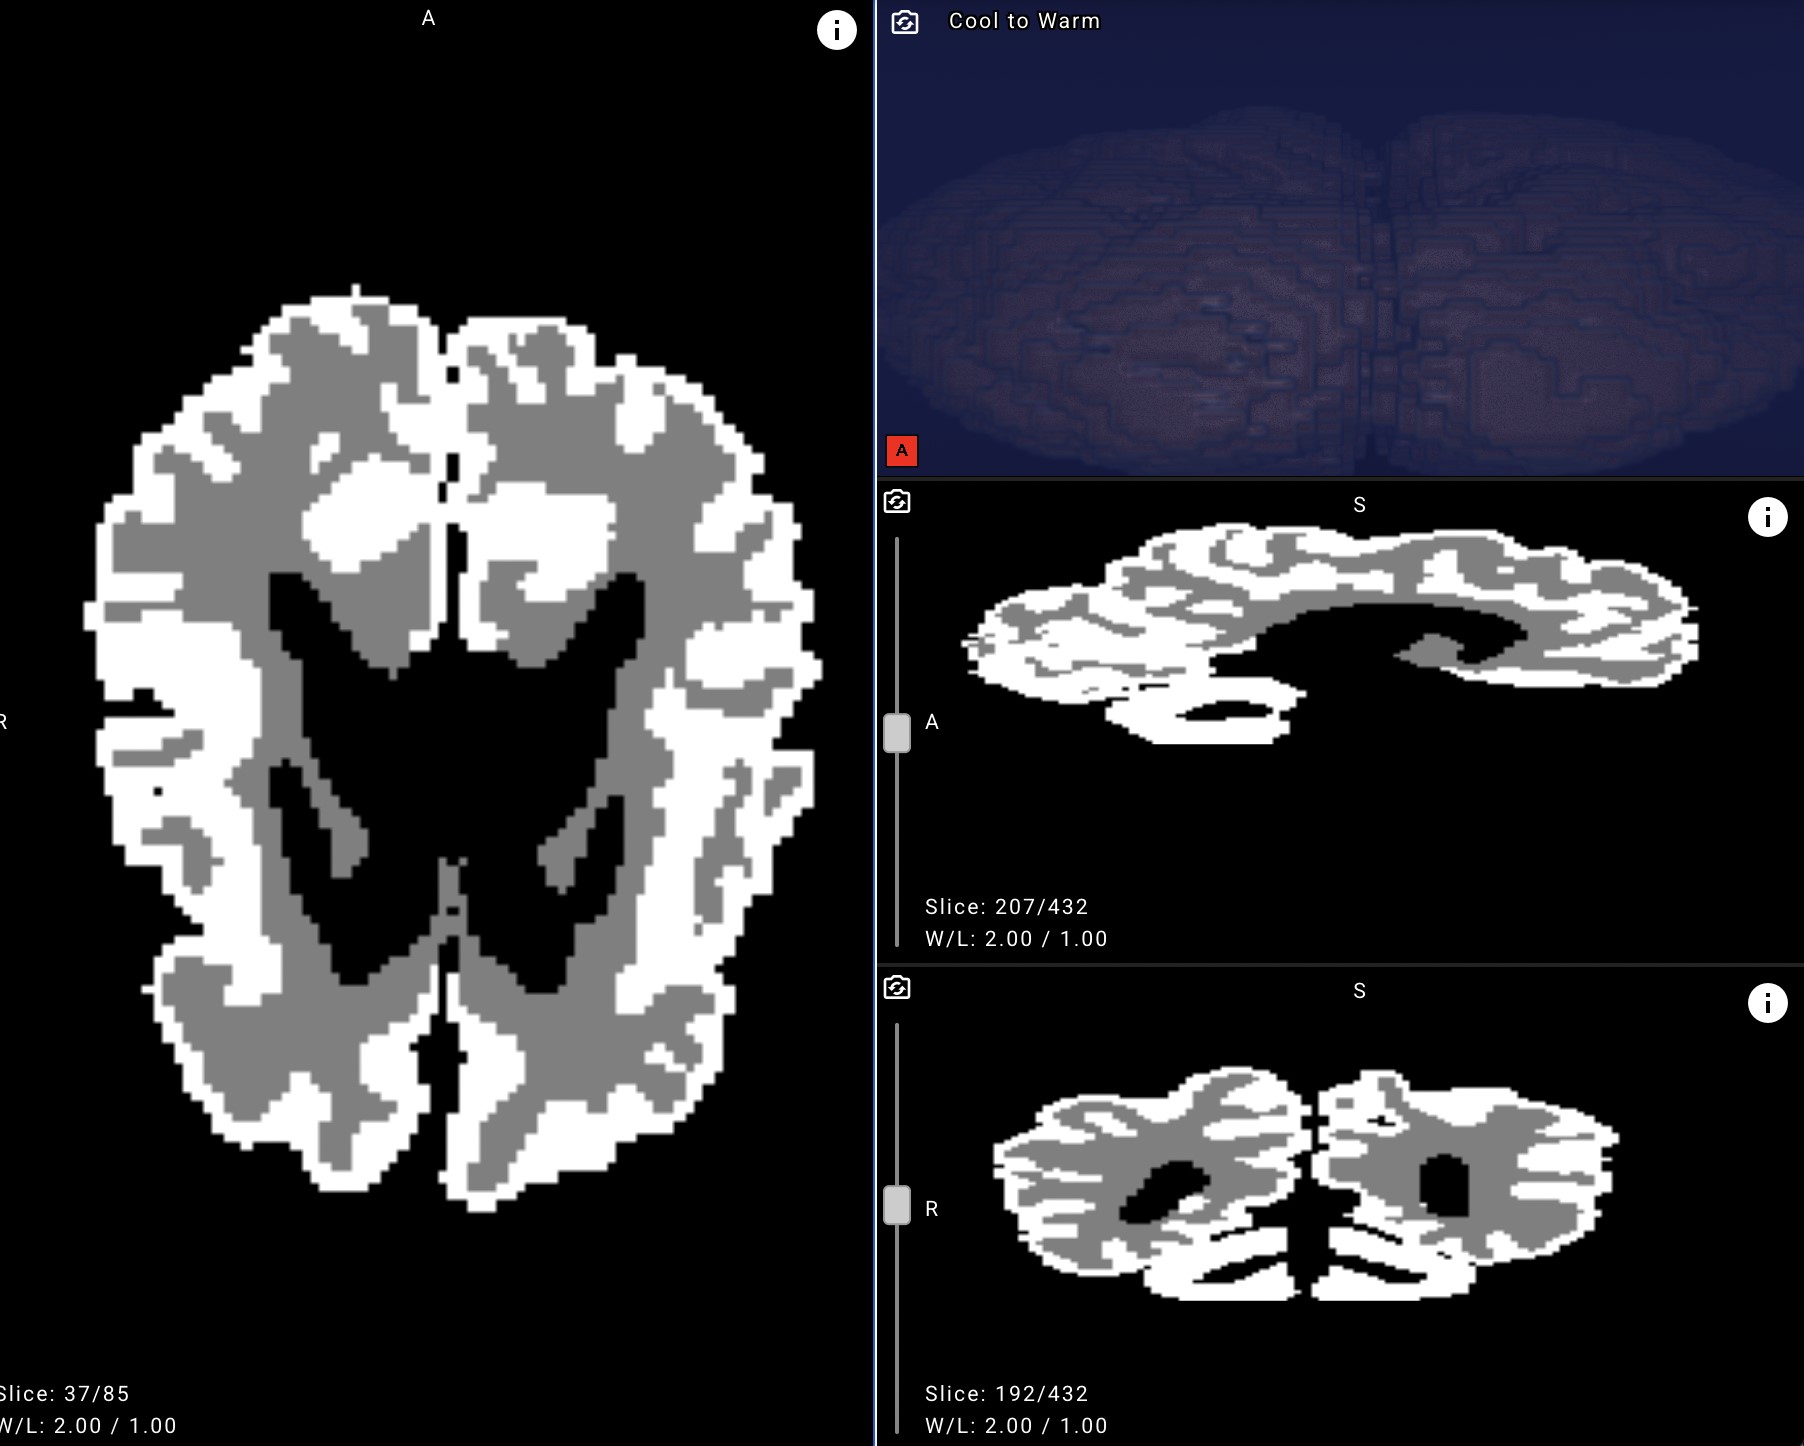

Example of an MRI brain image with white matter and gray matter masks applied after neural network processing.

The proposed solution analyzes MRI scans and can distinguish between gray and white brain matter with over 90% accuracy. Cutting evaluation time from days to minutes, it enables earlier detection and more effective rehabilitation planning for infants with cerebral palsy and other central nervous system disorders.

To bridge this gap, Yandex researchers collaborated with medical experts to create new annotations, design a dedicated neural network architecture, and run a series of machine learning experiments. The resulting model achieved over 90% accuracy in distinguishing gray and white matter in infant brains on internal evaluation data, demonstrating its potential for clinical use.

- Improve accuracy and objectivity. With over 90% accuracy, the model highlights outlines and quantifies the ratio of gray to white matter in an infant’s brain.